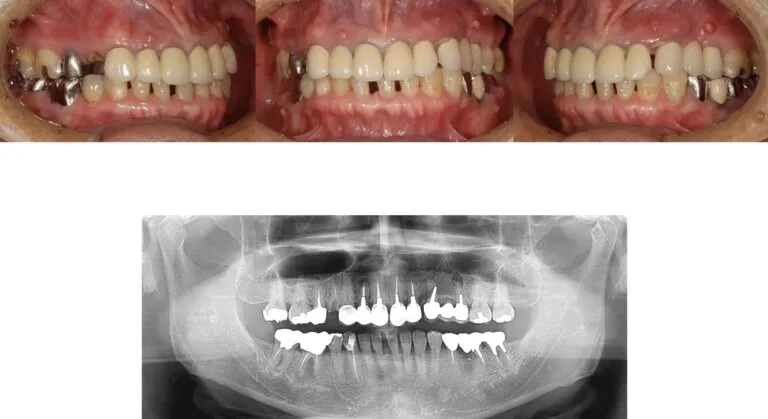

症例2

- 主訴

- 歯が取れた。全体的な治療を希望

- 治療内容

- インプラント治療、下顎前歯の部分矯正、セラミックによる補綴治療

- 治療費

- 400万

- 治療期間

- 1年6ヶ月

- 通院回数

- 60回

- 想定されたリスク

- 歯根破切や補綴装置の脱離

- コメント

- これまで局所的な治療の繰り返しを受けてきていた為、噛み合わせなども考慮して全顎的に整えることができた

before

after